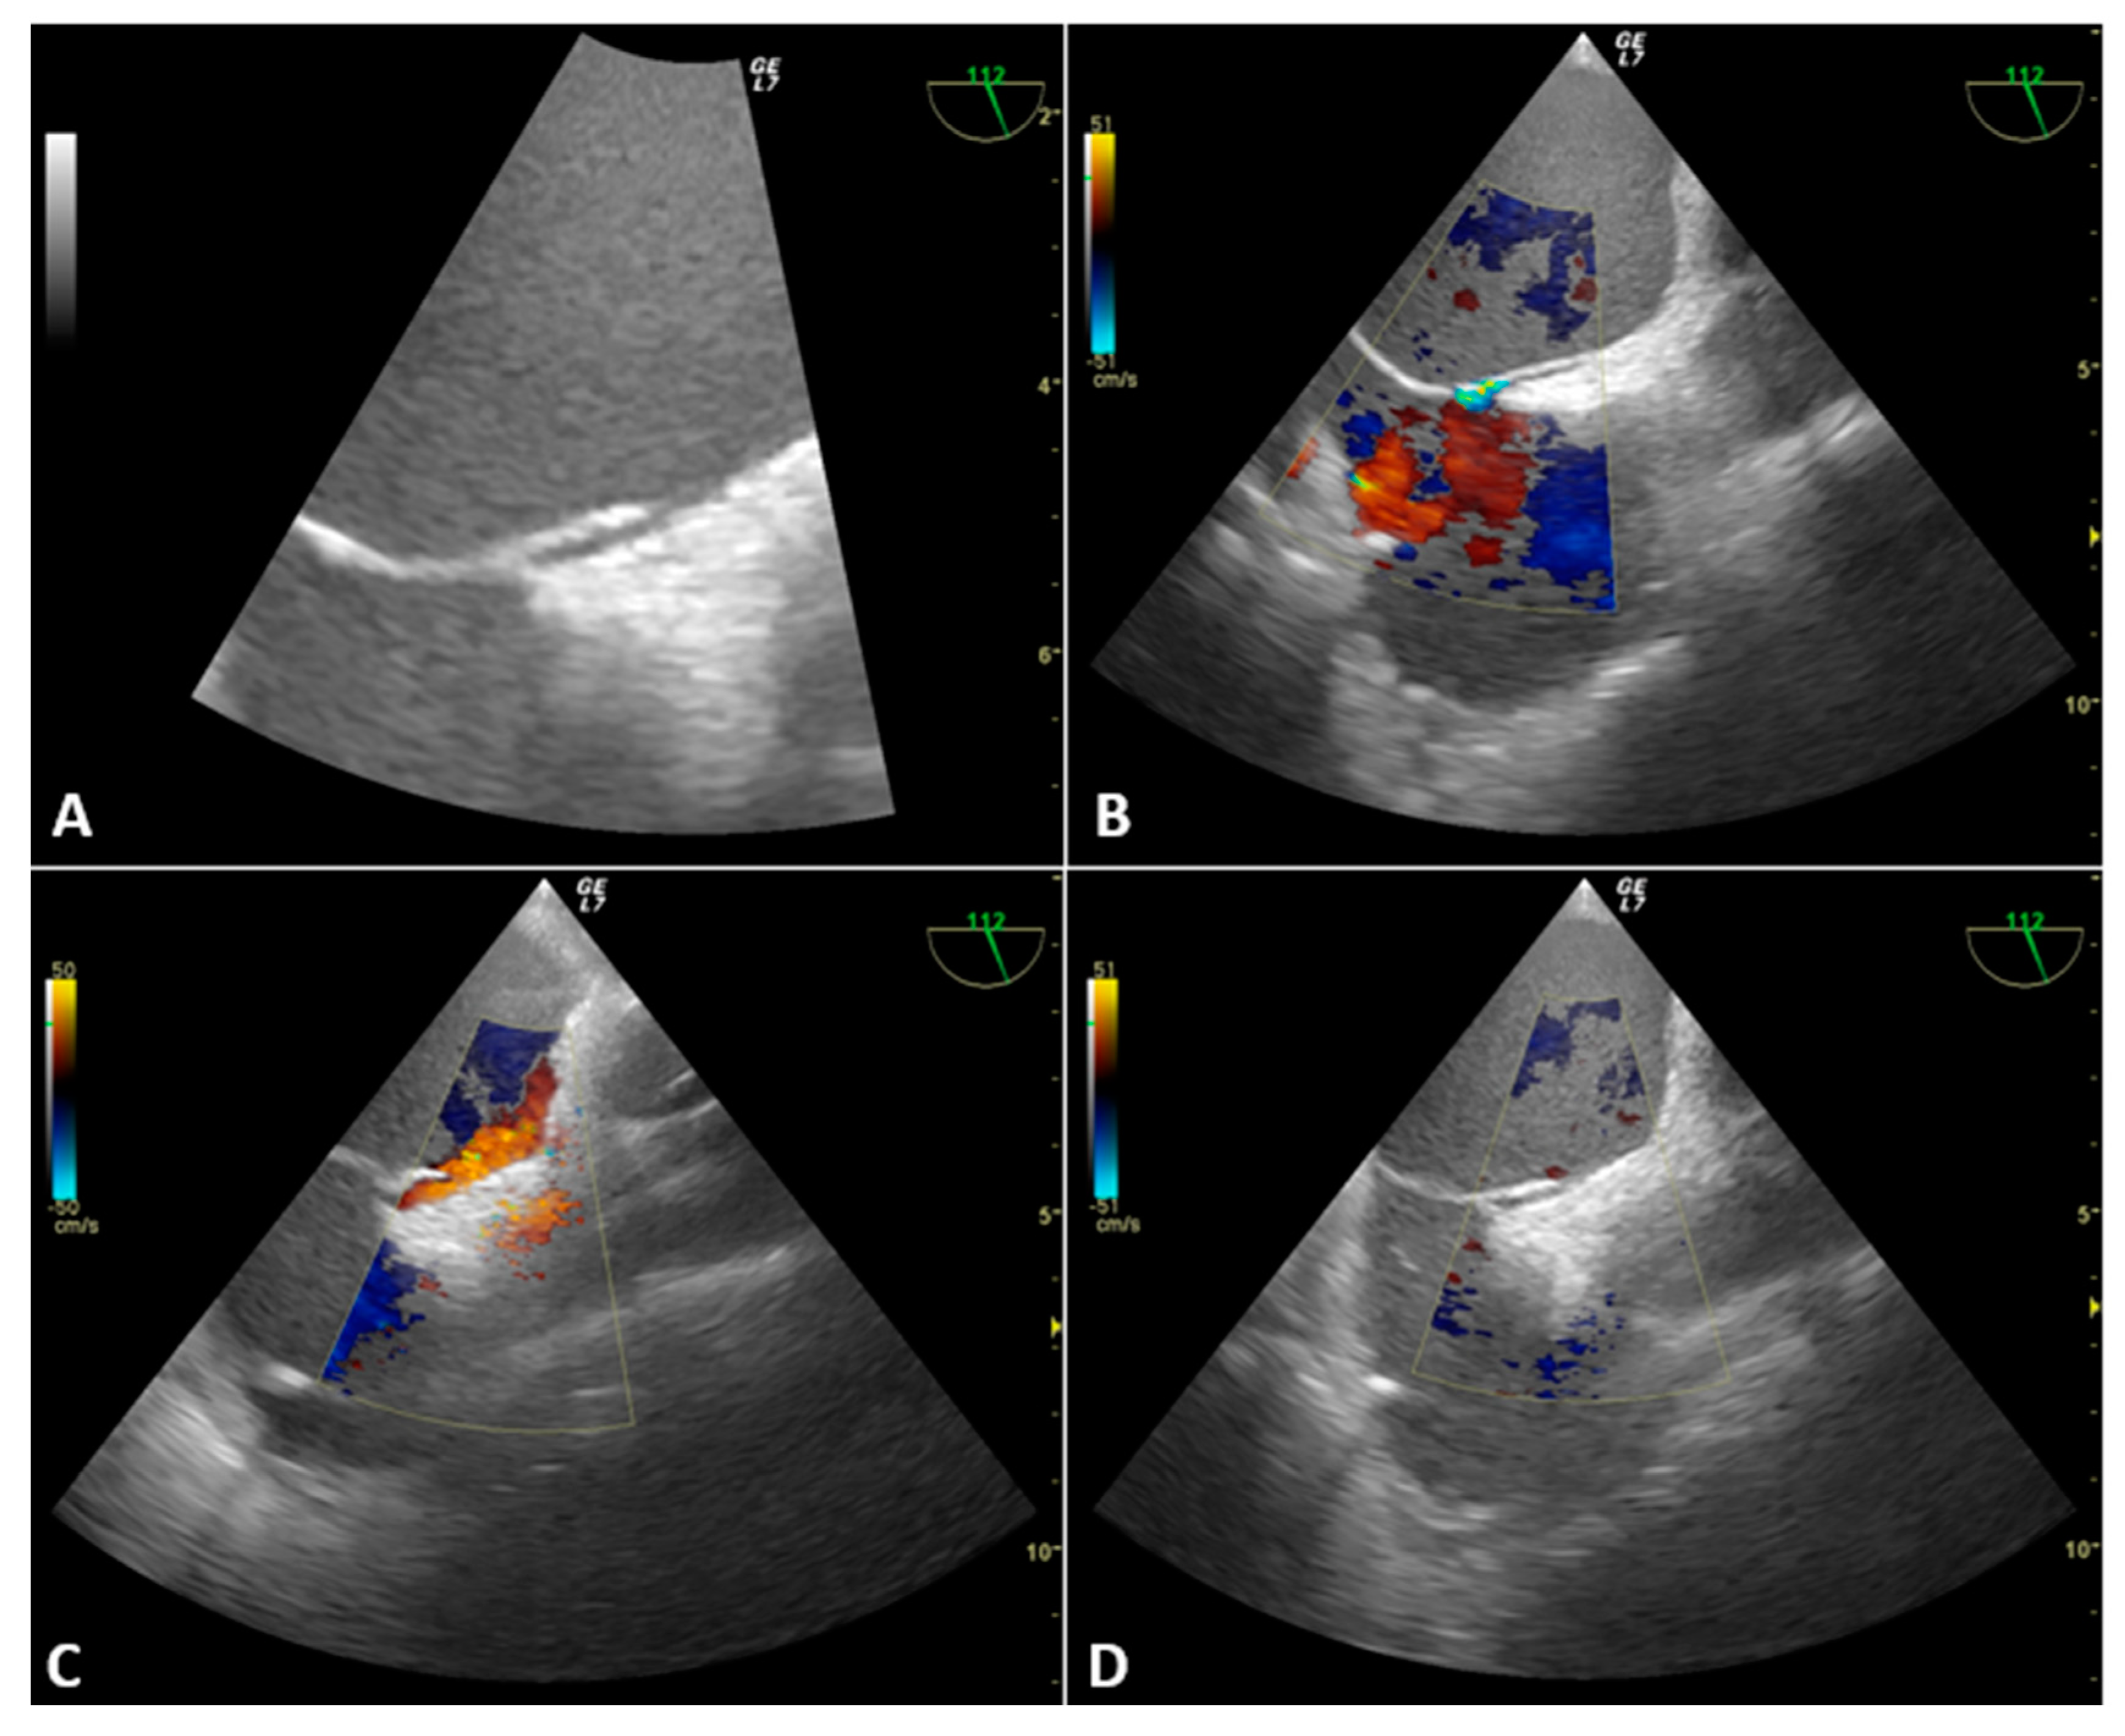

3.2.1. Case 1

3.2.2. Case 2

3.2.3. Case 3

3.2.4. Case 4